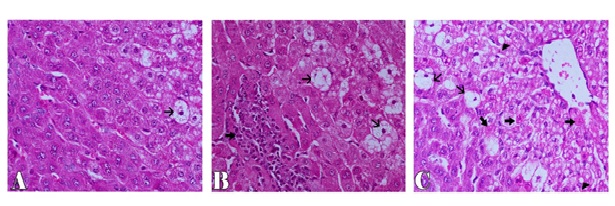

Microscopically, the examined liver of rabbits in first control group showed normal structure of the liver with distinct hepatocytes and sinusoidal spaces (Figure 1-A). In contrast, the histopathological examination of the liver of rabbits in fifth (CCl4 intoxicated) group revealed congestion of central veins with severe hepatocellular damage represented by diffuse macrovesicular and microvesicular steatosis and ballooning degeneration of hepatocytes including centrilobular, midzonal and periportal areas with apoptosis of hepatocytes (Figure 1-B). The apoptotic hepatocytes showed hypereosinophilic cytoplasm and fragmented nuclear material within the cytoplasm (Figure 1-C). Some of these cells were surrounded by a clear halo due to contraction of the apoptotic hepatocytes (Figure 1-D). In addition, focal areas of hepatic necrosis were also coexisted with apoptosis of hepatic cells. Mutiple mononuclear inflammatory cellular infiltration of hepatic parenchyma particularly lymphocytes were seen. Moreover, the examined portal areas showed bile ductal hyperplasia with degereneration of their lining epithelium (Figure 1-E). The microscopic examination of liver of rabbits in second group (silymarin + CCl4) revealed only mild hepatic lesions in the form of vacuolar, hydropic and ballooning degeneration of some hepatic cells (Figure 2-A). Also, the examined liver of rabbits in third group (100 mg mentha + CCl4) showed significant improvement in the microscopic pictures compared with those of CCl4 induced hepatotoxicity group where mild hepatic damage characterized by hydropic and ballooning degeneration of some hepatocytes in centrilobular areas with focal mononuclear inflammatory cellular aggregation among hepatic parenchyma was seen (Figure 2-B). In fourth group,pretreatment with 50 mg mentha was also associated with improvement of liver microscopic picture, where the hepatic damage was restricted to centrilobular areas and characterized by hepatic steatosis and ballooning degeneration of hepatocytes with apoptosis of individual scattered hepatocytes (Figure 2-C).

Figure 2. Liver of rabbit showing  ballooning degeneration of few hepatic cells (thin arrow) in  CCl4+silymarin group (A), focal mononuclear inflammatory cells aggregation (thick arrow) and ballooning degeneration of some hepatocytes (thin arrow) in CCl4+100 mentha group (B), ballooning (thin arrows), fatty degeneration (arrowhead) and apoptosis of hepatocytes (thick arrows)  in CCl4+50 mentha group (C). H&E stain X200.